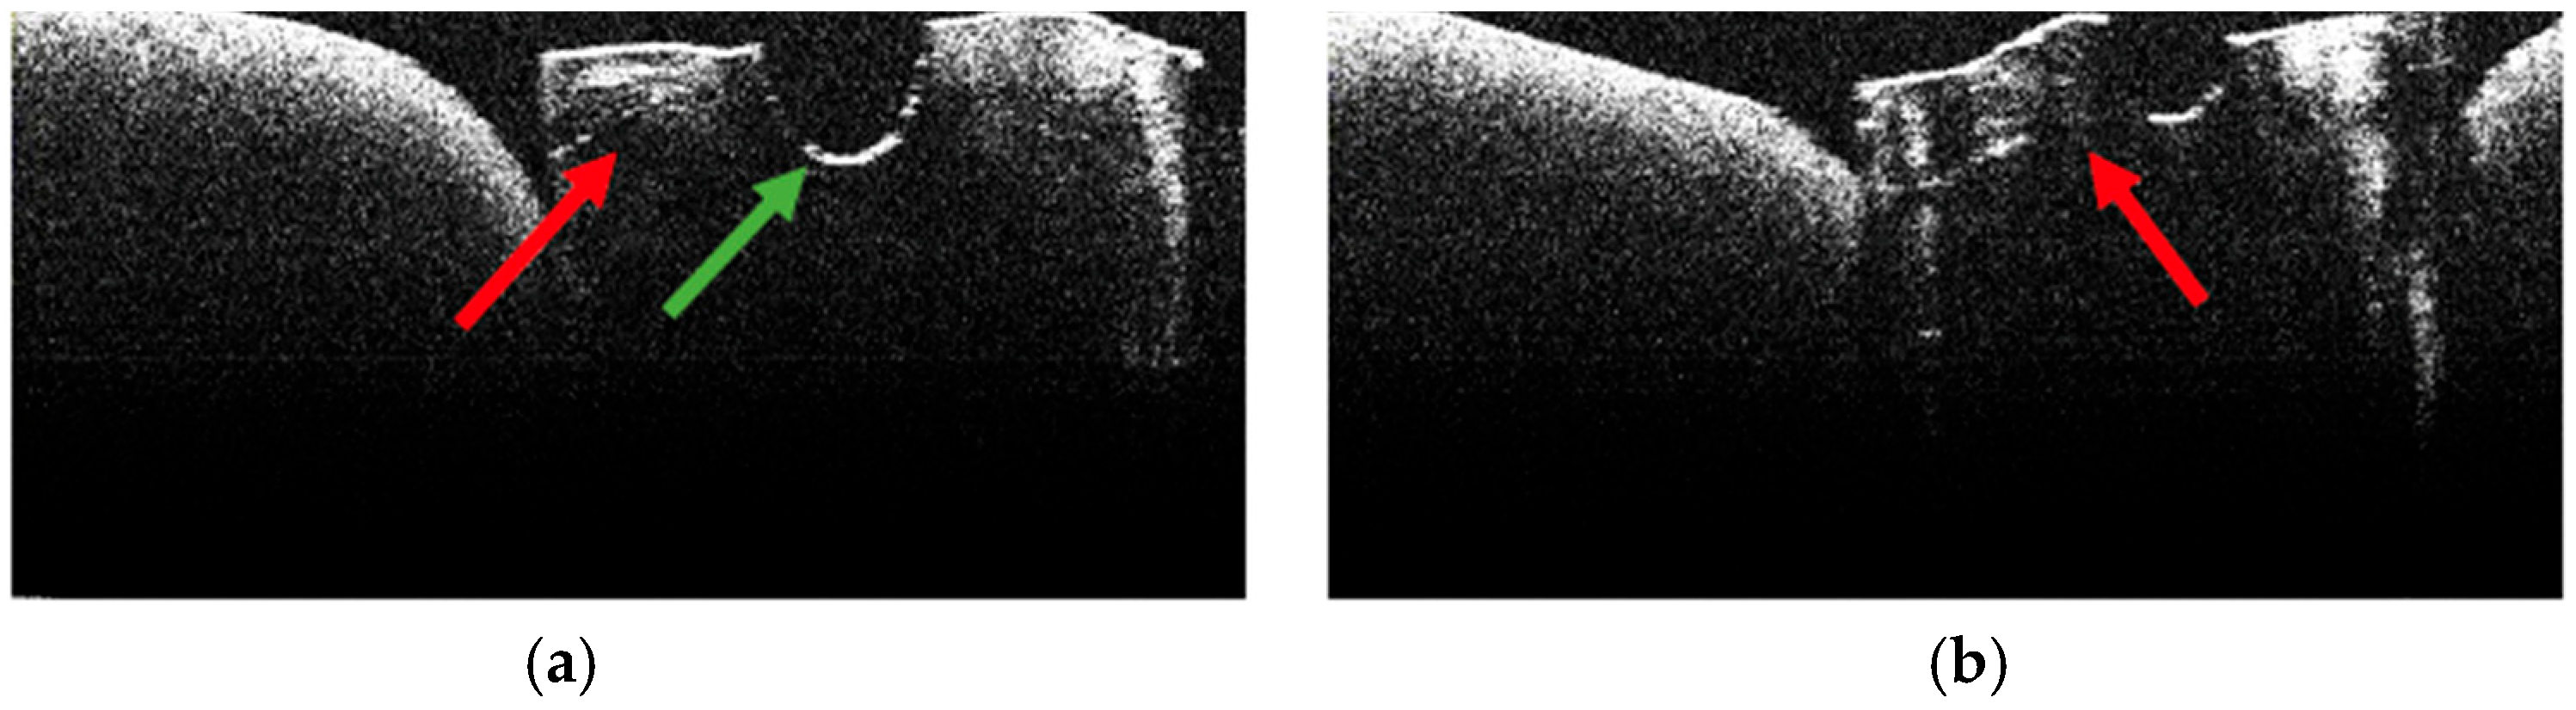

3.2. Defining OCT Signatures: Alterations vs. Artefacts

3.5. OCT Examination of Specimens from Group B

3.6. Topographic Distribution